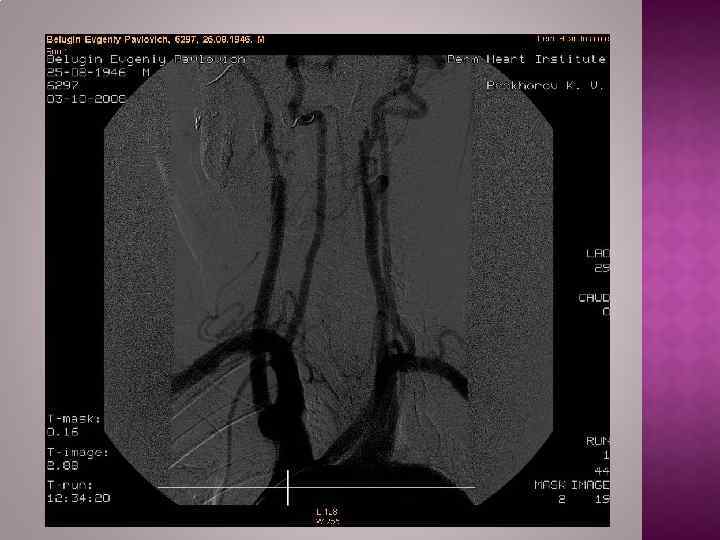

Рентгенологическим признаком аневризмы грудной аорты является наличие гомогенного образования с ровными четкими контурами, не отделимого от тени аорты и пульсирующего синхронно с ней. Трансторакальная эхокардиоаортография дает возможность выявить аневризмы восходящего отдела и дуги аорты, определить их размеры, наличие фенестрации интимы и расслоения аорты, аортальной регургитации. Чреспищеводная эхокардиоаортография позволяет еще лучше распознать патологию аортального клапана, синусов Вальсальвы, устий коронарных артерий, тубулярной части восходящей аорты, а главное — диагностировать расслоение аорты с выявлением внутренней мембраны и проксимальной фенестрации. Компьютерная томография и магнитно-резонансная ангиография позволяют определить локализацию и размеры аневризмы, наличие расслоения аорты и внутрианевризматического тромба, дать характеристику стенки аорты. Рентгеноконтрастная аортография по-прежнему является «золотым стандартом» в диагностике аневризм аорты. При грудных и особенно расслаивающих аневризмах необходимо выполнять контрастирование всей аорты (панаортография) с определением локализации аневризмы, взаимоотношения ее с магистральными ветвями, наличия фенестрации и расслоения.